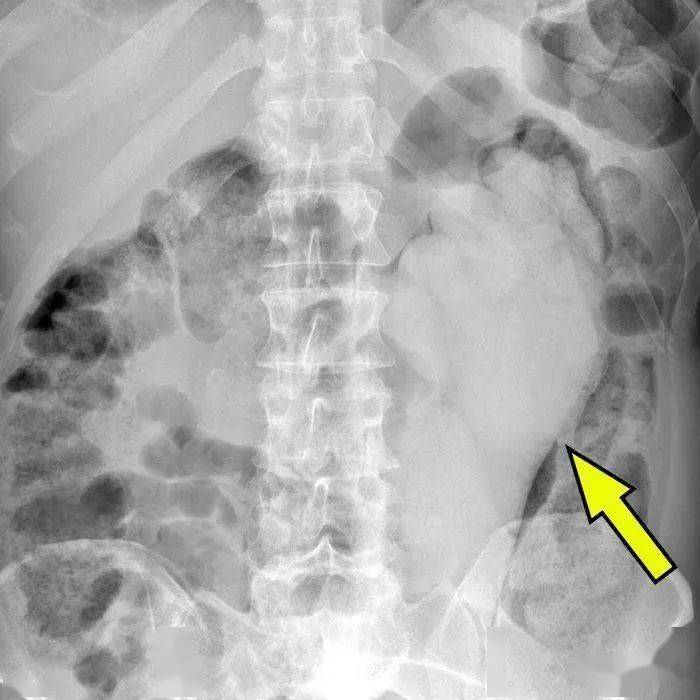

“带盖的剃须膏 。 ”